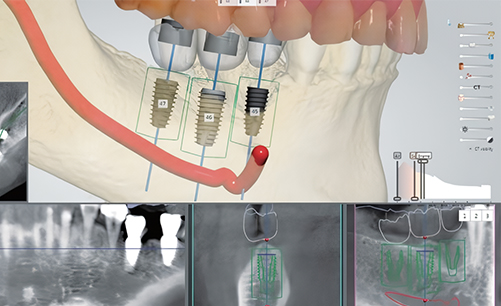

Digital Navigation Implant Procedure

A virtual simulation surgery is conducted based on 3D CT data

to plan the optimal implant placement position.

A custom surgical guide is then fabricated to enable

highly accurate implant placement.

Digital navigation implant technology enables precise implant placement exactly at the pre-planned position.